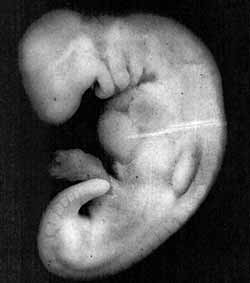

比较水蛭与血块阶段的胚胎,我们发现两者有相似之处2,如图 1 所示。 另外,此阶段的胚胎从母亲血液中获取营养,就像水蛭从其它生物身上吸血维持生命一样。3

图 1

图 1: 说明水蛭与人类胚胎在血块阶段相似之处的图组。(根据Human Development as Described in the Quran and Sunnah [古兰经与圣行中所描述的人类发育] 所绘之水蛭图,作者莫尔 (Moore) 等,第 37 页,修改自 Integrated Principles of Zoology [动物学综合原理],作者西克曼 (Hickman) 等。 根据 The Developing Human [发育中的人类] 所绘之胚胎图,作者莫尔 (Moore) 与佩尔绍德 (Persaud),第 5 版,第 73 页。)